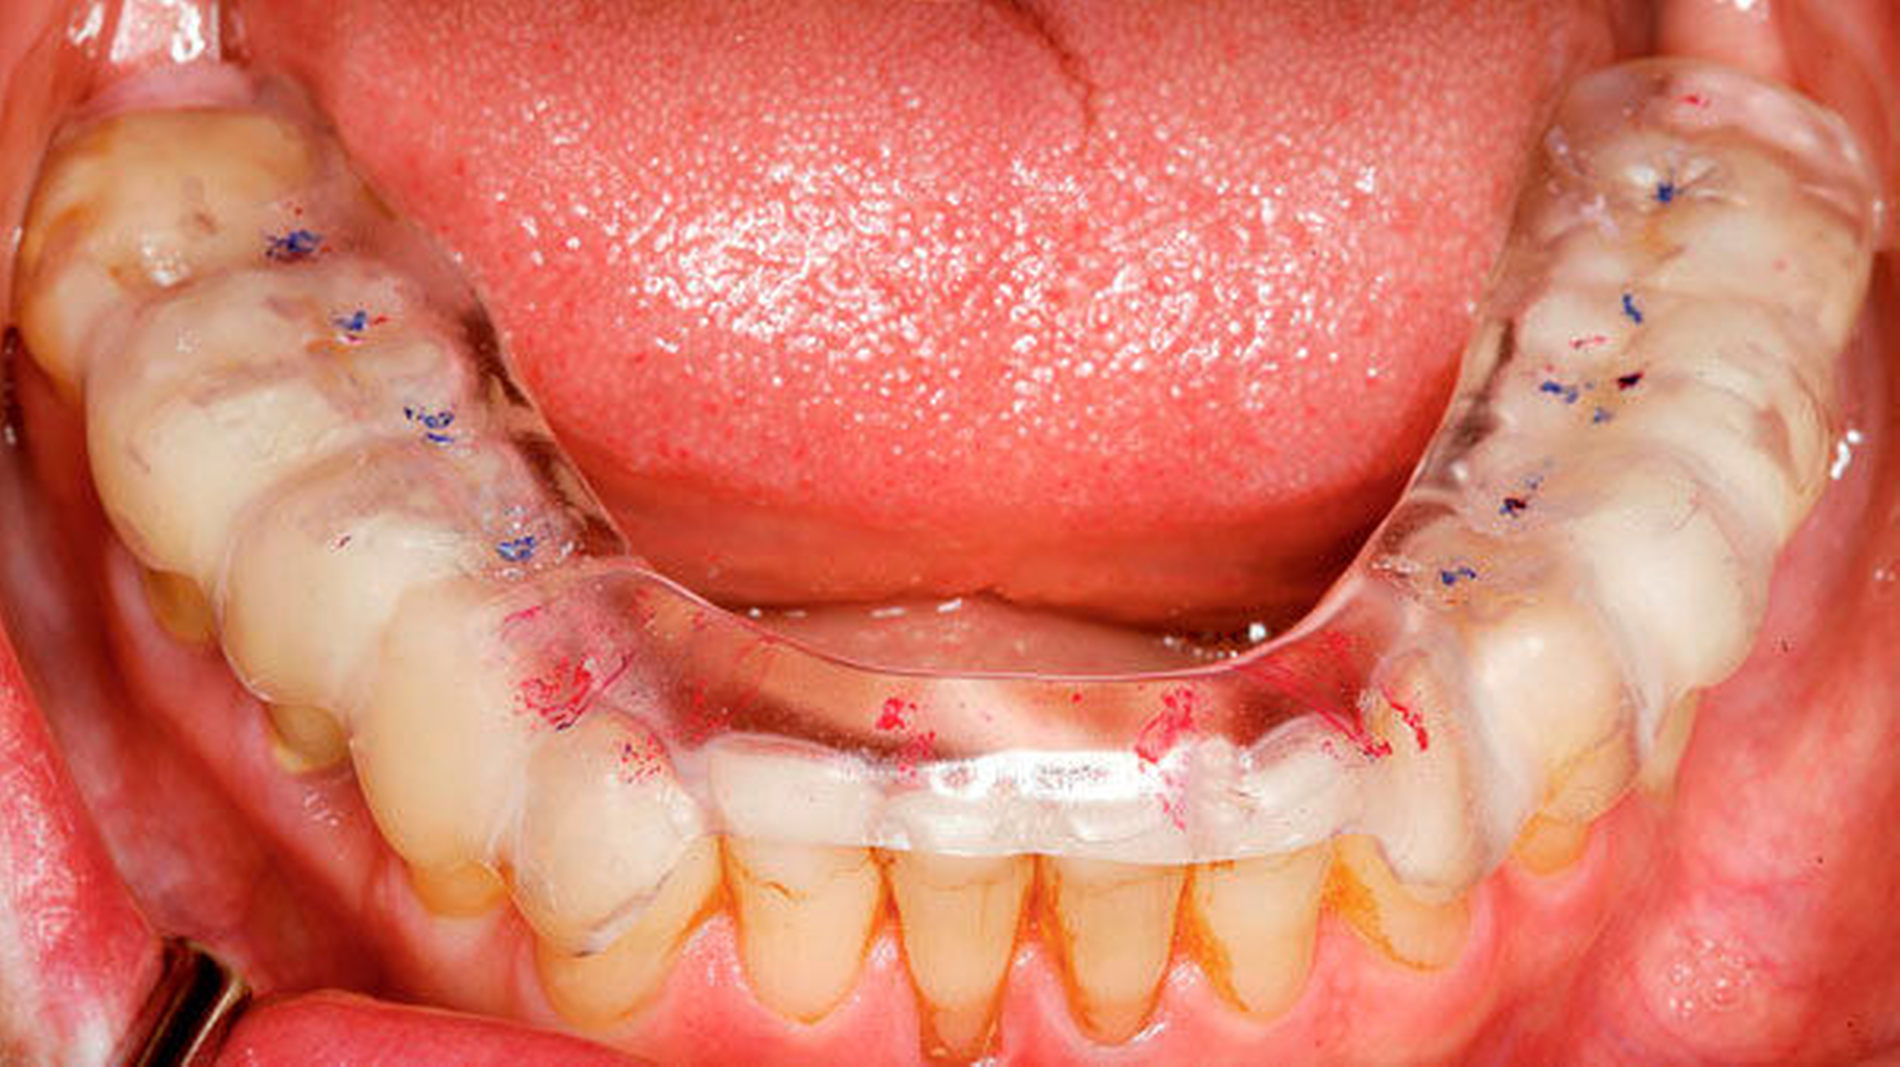

Eingefärbte Schienen können zur Darstellung nächtlicher Bruxismusaktivitäten in Form von Abriebmustern genutzt werden [Ommerborn et al., 2015]. Die Leitlinie weist aber darauf hin, dass damit Schlafbruxismus in Form von Pressen unerkannt bleibt und f ü r Mehrschichtschienen keine ausreichende Evidenz zur Diagnostik von Schlafbruxismus besteht.

Okklusionsschienen gelten als reversible okklusale Ma ß nahmen, die eher symptomatisch eingesetzt den Abrieb der Z ä hne bei Schlafbruxismus verhindern helfen (Abbildung 4). Nachgewiesen werden konnte auch eine Reduktion der Kaumuskelaktivit ä t durch Schienen, dies jedoch nicht regel- und dauerhaft [Guaita et al., 2016; Manfredini et al., 2015]. Vielmehr wird eine intermittierende Trageweise empfohlen, um diesen Effekt auf die Muskulatur zu erzielen [Jokubauskas et al., 2018]. Die Wirkung der Schiene beruht auf einer Veränderung neuromuskulärer Reflexe und einer veränderten Rekrutierung von Muskelfasern durch die veränderte Okklusion [Ispirgil et al., 2018]. Treten jedoch Gewöhnungseffekte auf, verliert sich dieser Effekt.